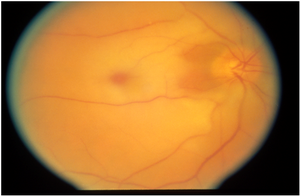

في انسداد الشريان الشبكي المركزيCRAO فإن الموجودات الكلاسيكية من ابيضاض في الشبكية و علامة الكرزة الحمراء بسبب التغيم في طبقة الألياف العصبية كما أنها تصبح متوذمة بسبب الإقفار . واللطخة تعطي علامة الكرزة الحمراء لأنه لا يوجد طبقة من الألياف العصبية تغطيها . هذه الموجودات ربما تحتاج الى ساعات لكي تظهر والوذمة تدل على إنذار رؤية سيء . وخلال شهر من سير الحالة تزول الوذمة وتضمر الشبكية الداخلية .

- انسداد الشريان الشبكي المركزي CRAO: لديه علامة التقطع Boxcarring وابيضاض في الأرباع الأربعة , مع قدرة بصرية عادة بين 200/20 و حركة يد .

- انسداد الشريان العيني : نلاحظ فيه موجودات ال CRAO وكذلك الإقفار الوعائي المشيمي . القدرة البصرية عادة انعدام حس الضياء . لا يوجد علامة الكرزة الحمراء طالما يوجد انسداد في تروية المشيمية .

- التسمم بأول أكسيد الكربون يمكن أن نشاهد علامة الكرزة الحمراء .